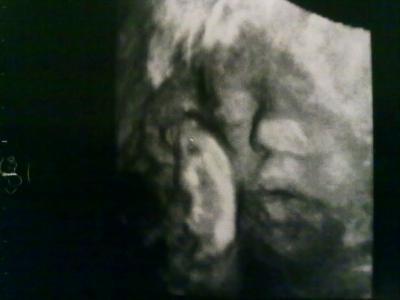

Heute hatte ich meinen FA-Termin (30+6) und mein Kleiner zeigte sich mal wieder von seiner Schokoladenseite!

Hier einige Daten:

Größe: 38,29cm

Gewicht: 1478Gramm

Kopfumfang: 29,1cm

Bauchumfang: 25,51cm

Lage: II.Schädellage

Größe und Gewicht ist zwar im unteren Bereich der Perzentile, aber völlig in der Norm! Mein FA meinte auch, dass diese Werte passend zu meiner Größe und Figur sind!!!

Und dass ich in den letzten 5Wochen nichts zugenommen habe, ist auch nicht schlimm - schließlich ist mein Baby gut gewachsen!!!

Schön dass alles soweit ok ist bei euch! Das Foto soweit man was erkennt ist ja lustig - macht deine Maus einen "Ohhhh-Mund" ;-) GLG

Ja... mein Kleiner hatte immer den Mund offen!!!